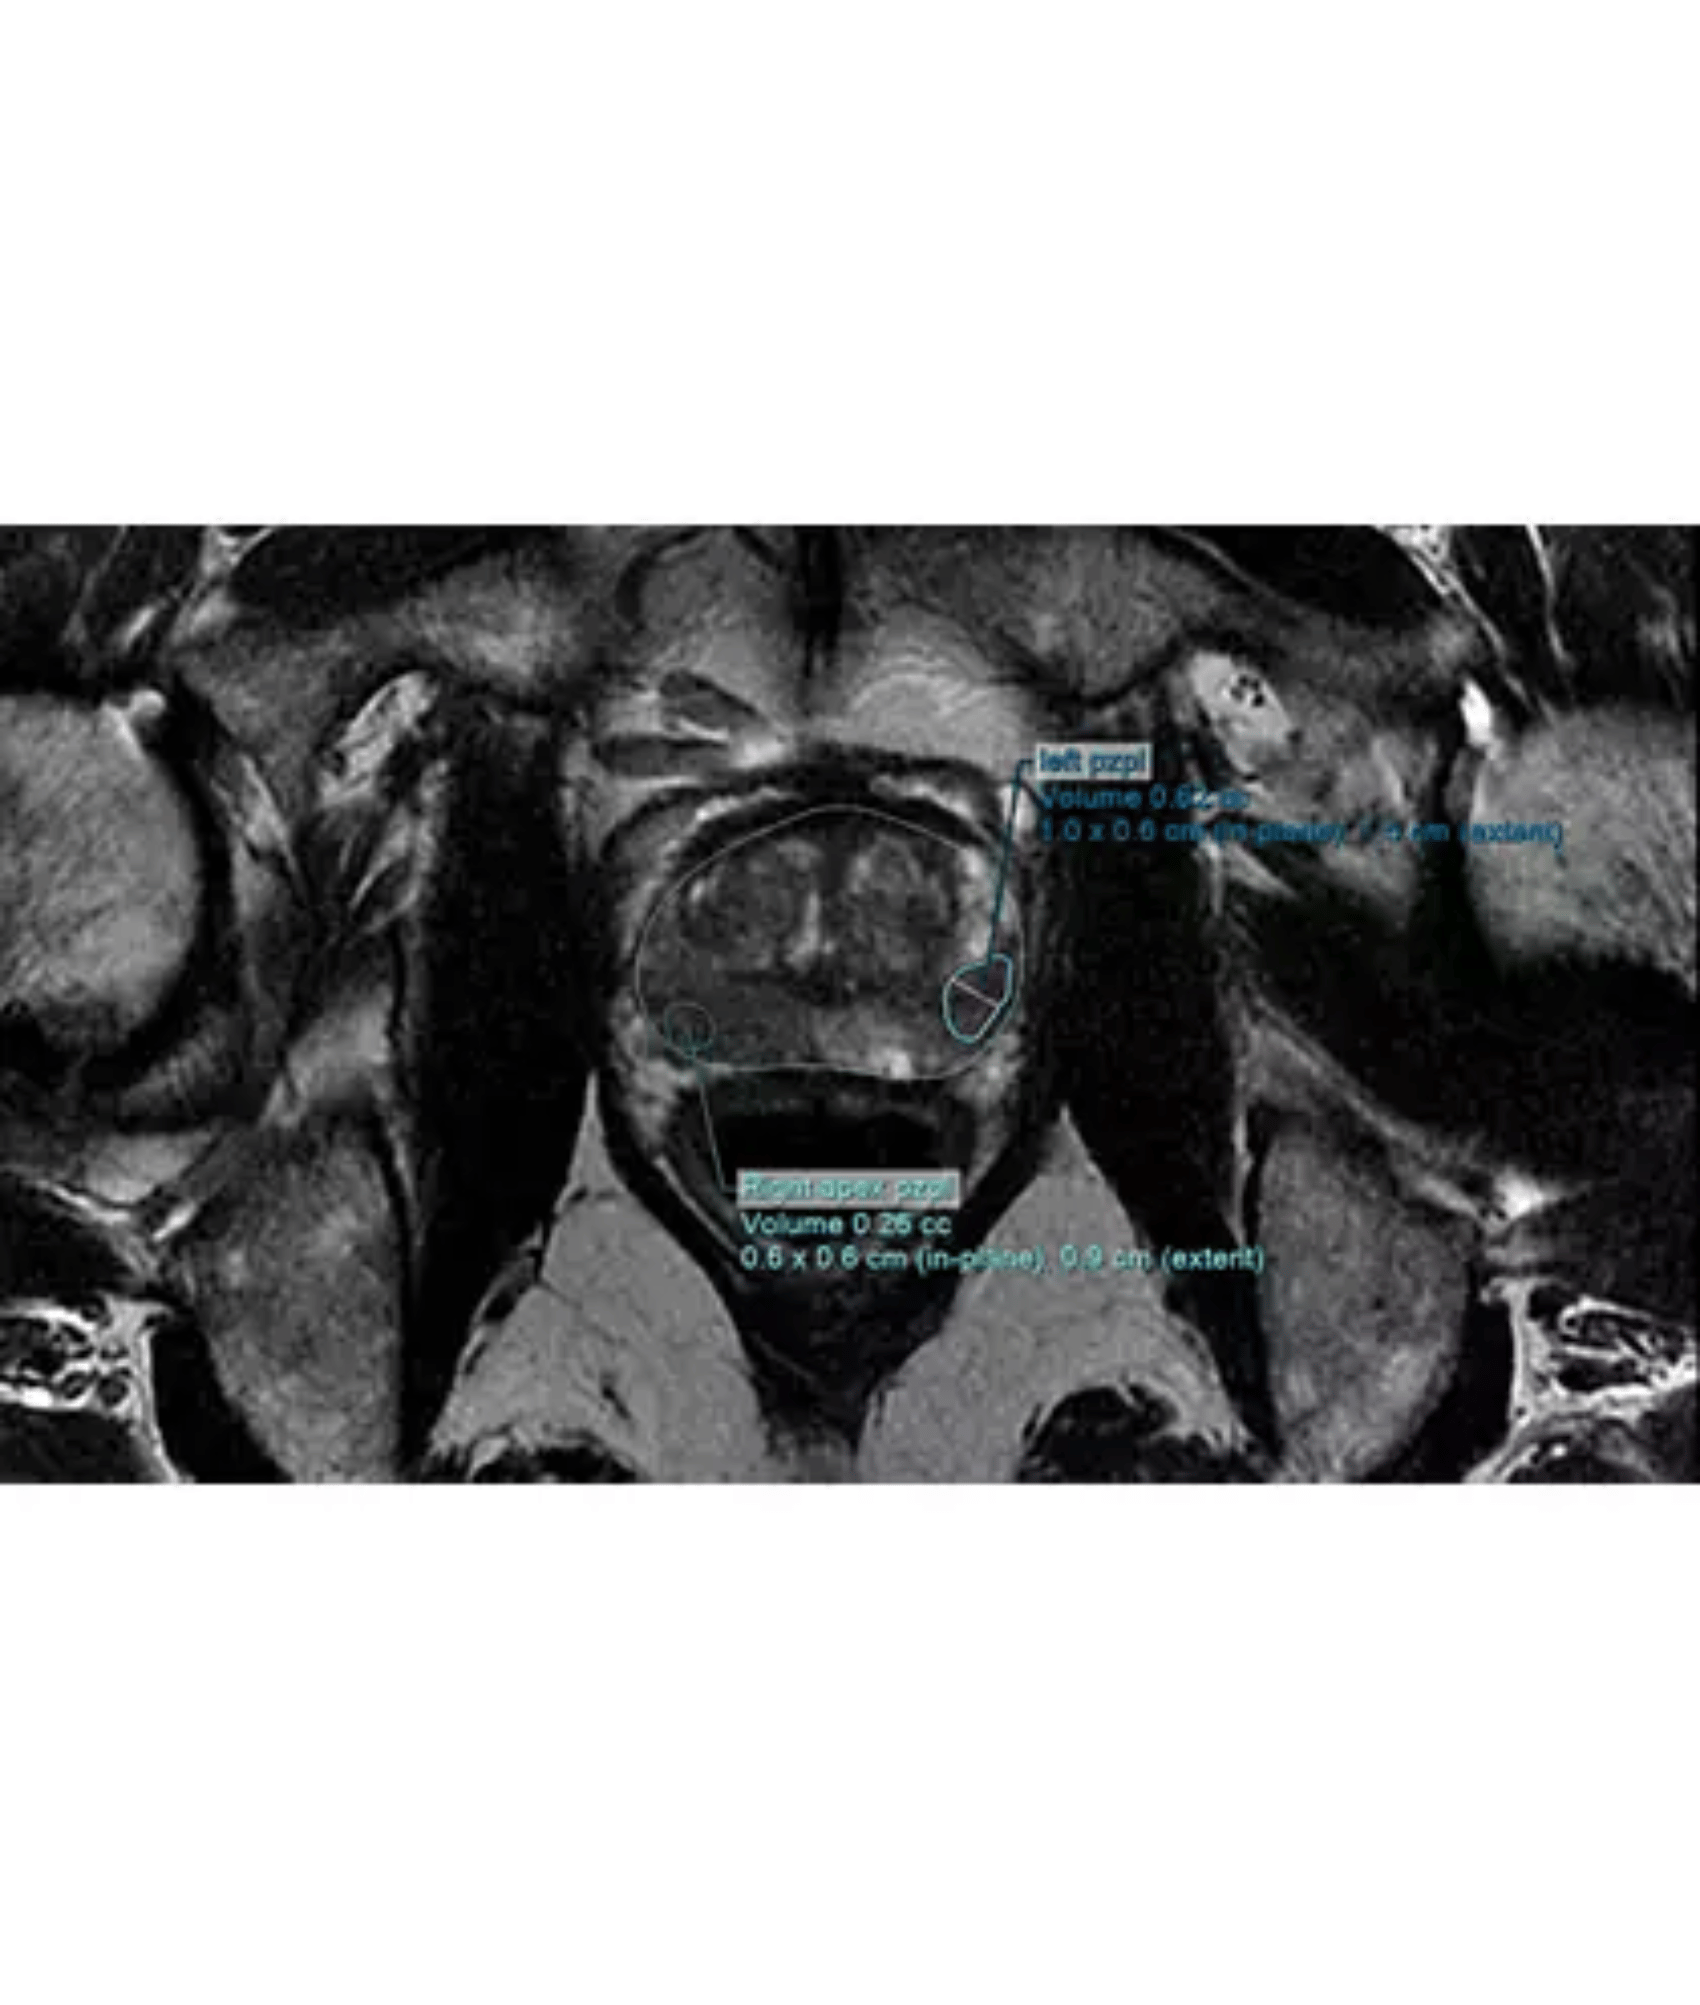

DynaCAD

Philips DynaCAD Prostate je pokročilý systém, který poskytuje komplexní sadu nástrojů pro analýzu prostaty v reálném čase.